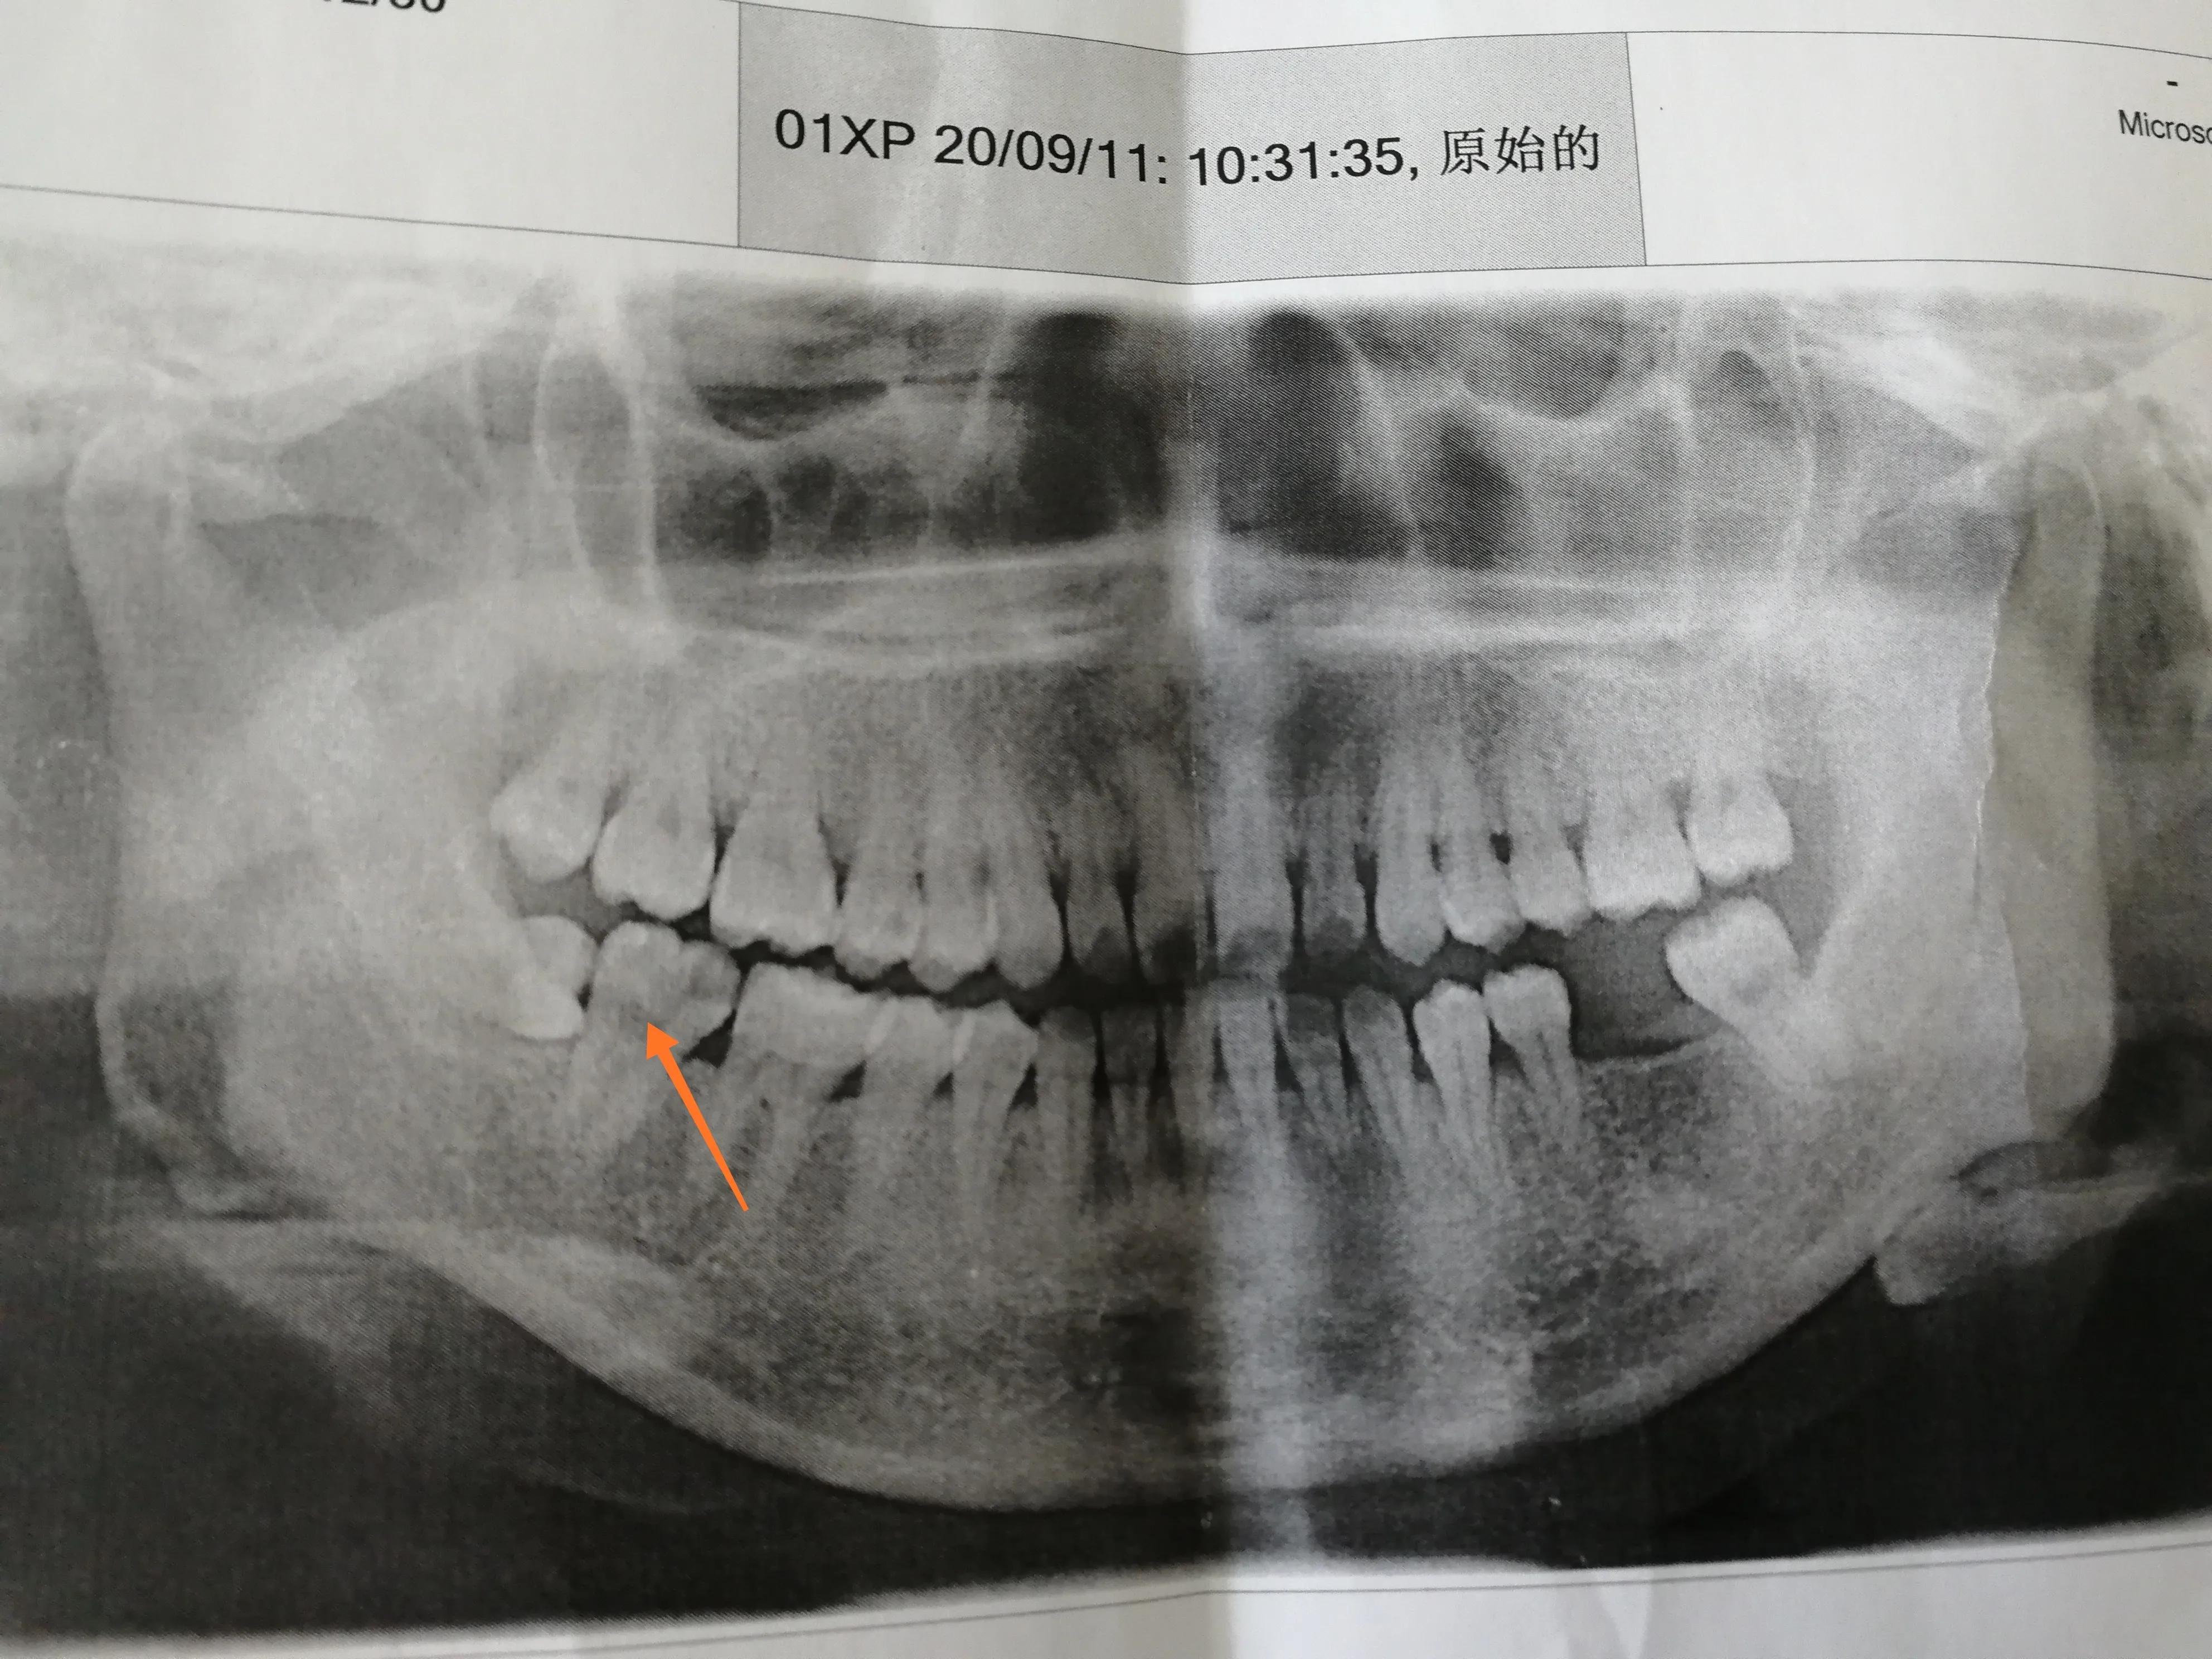

首先来张证件照[呲牙]我残缺不全的一口牙呀这次治疗的是右边最后一颗大牙,就是图片箭头所指的那颗牙。这颗牙其实已经烂了蛮久了,也掉了很大一块,去年,也就是疫情前我就去东方医院看过,说是只能根管治疗。当时年纪轻不懂事,胆子还小。百度完根管治疗后,直接吓回家了,再也没去过医院[我想静静]。直到今年8月,这颗牙又隐隐的疼了起来。当时刚好有同事去同济口腔做完了根管,说是完全不疼,终于鼓足了勇气开始了预约挂号治疗之旅。(其实还是怂了的,前期还是挂了牙周病科探探路,医生用麻药还是很“舍得”,才放心的预约了后续的治疗)。